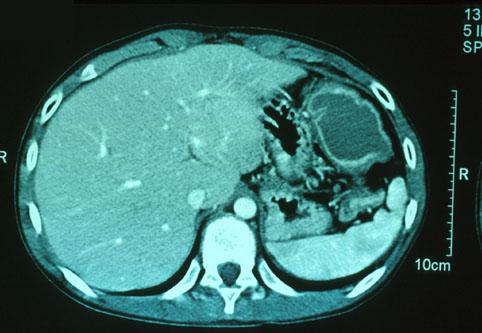

clasificación del pacienteTumor Epitelial Maligno/Adenocarcinoma

parte(separada por órganos)colon/transverso

método de exámenTAC

clasificación ectoscópica de tumoresTipo 2(Tipo ulcerado de bordes claros)/

diámetro mayor del tumor30 - 34

grado de penetraciónss(a1)